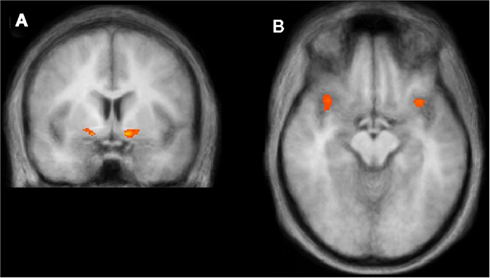

The ventral striatum (left) and the anterior insula (right) are involved in generating subjective happiness ratings.Taken from Grygolec et al., 2012, Frontiers in Psychology – http://tinyurl.com/mllbyzc

So; it looks like the ventral striatum might be doing, or at least reflecting, some of the sums that contribute to changes in happiness. But what about the product – where in the brain predicts how happy people actually say they are? Robb showed a different area, called the insula, predicted how responses to the question ‘How Happy Do You Feel Right Now?’. The insula is another celebrity in the study of brain systems of emotion – it seems to be involved in the process of interoception (the process of thinking about how your body feels), and emotional awareness. Again, it seems to go awry in emotional disorders – the awesome Helen Mayberg recently published the exciting finding that you could predict the most effective treatment for depression by looking at insula activity in depressed individuals (you can read a nice summary here).